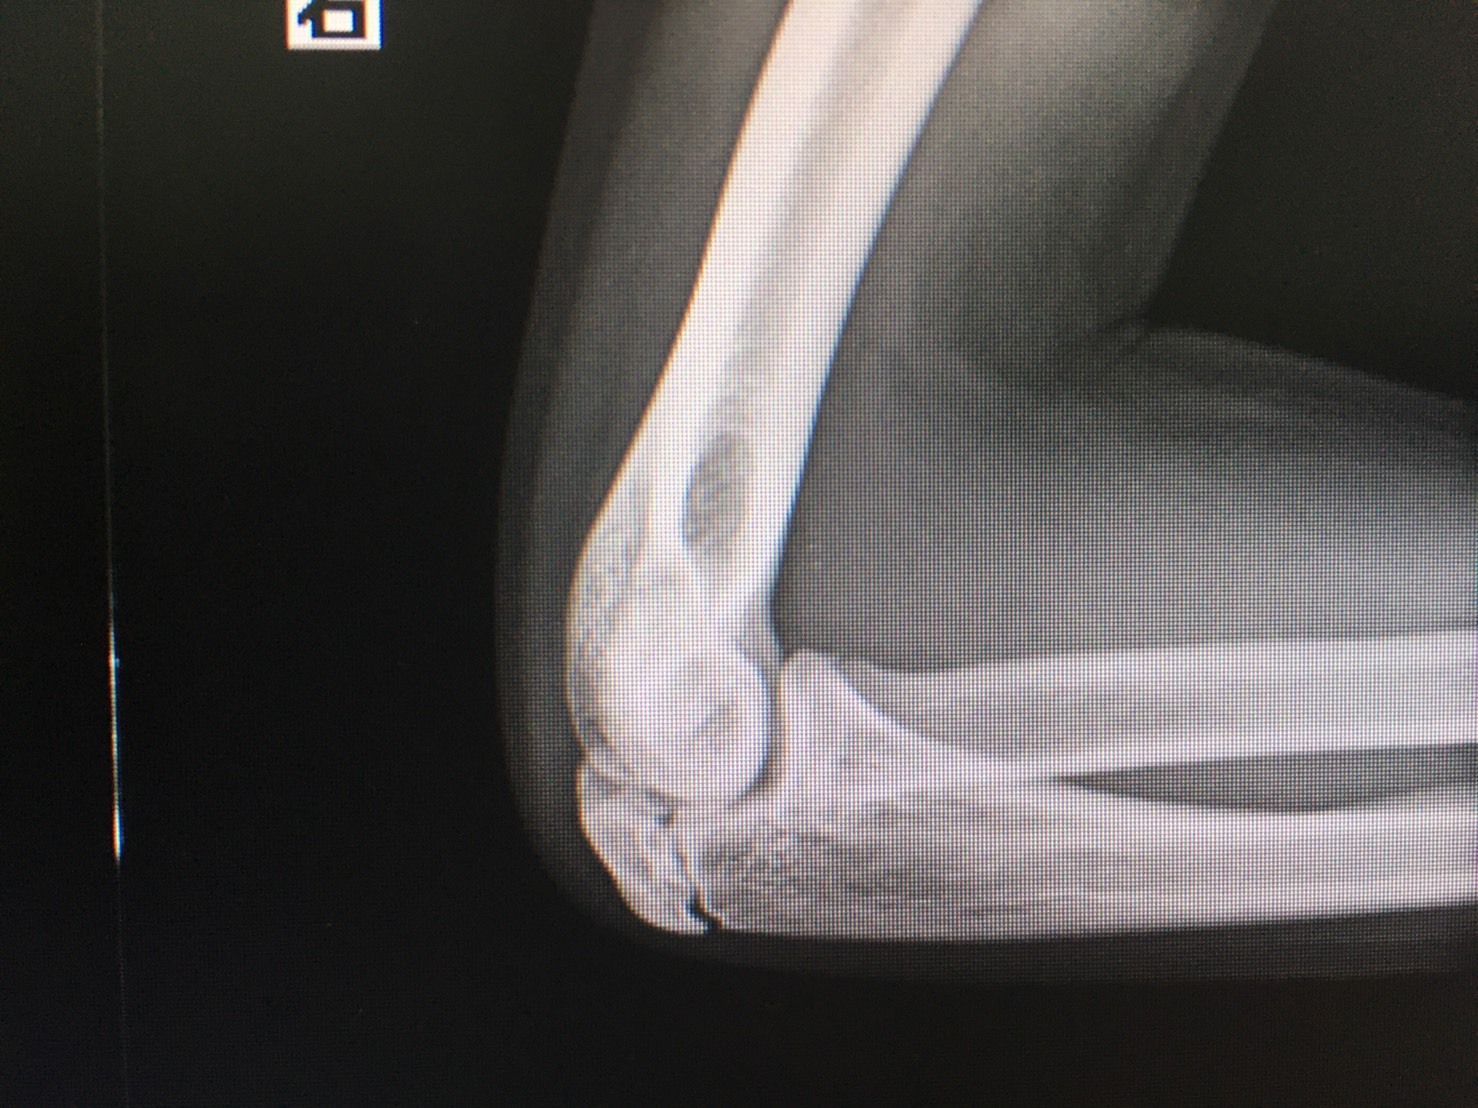

後方型野球肘の診断と治療

診断

後方インピンジメント障害の診断には、レントゲン検査やCT検査、MRI検査が有用です。